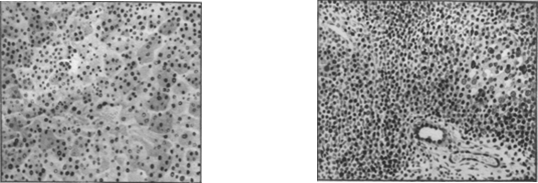

(рис. 1 и отд. табл., рис. 3).

В III фазе

(период выздоровления) перипортальные инфильтраты уменьшаются, убывает

количество некротизированных печеночных клеток, нарастают процессы

амитотического деления клеток. Внутрпдольковая пролиферация мезенхимальных

клеток стихает, становится более очаговой и узелковой.

Еще

некоторое время после клинического выздоровления о незаконченности процессов

восстановления свидетельствуют: лимфогистиоцитарные инфильтраты в портальной

зоне (рис. 2), полиморфизм печеночных клеток, обилие многоядерных печеночных

клеток, наличие липофусцина, а иногда и железосодержащего пигмента в

ретикулярных клетках и наличие желчных тромбов в отдельных желчных капиллярах.

Рис. 1. Печень при острой форме болезни Боткина

(мальчик 1 года 3 мес.). Дискомплексация печеночных балок. Некрозы

отдельных печеночных клеток. Пролиферация ретикулярных клеток. Рис. 2.

Печень при острой форме болезни Боткина (мальчик 1 года 8 мес.).

Значительная воспалительная инфильтрация портального тракта. Регенерация